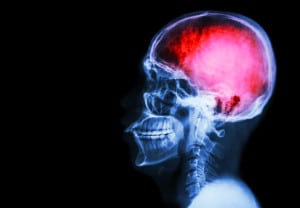

Epidemia Silenciosa: contución cerebral

Un simple golpe en la cabeza puede tener consecuencias a nivel neurológico que seguro no imaginabas. Te decimos cómo tratar...